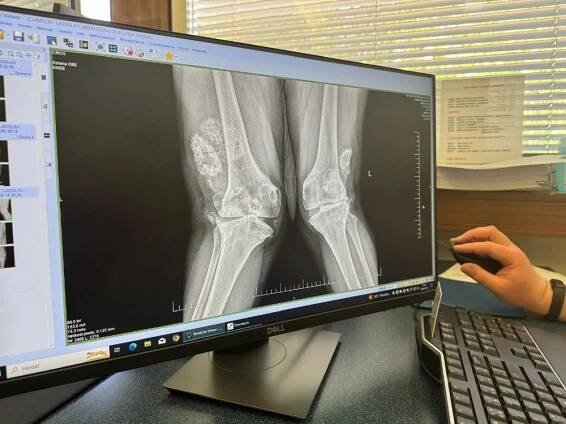

Ladislav Chmelík výměna kolenního kloubu

Výměna kolenního kloubu měla Láďovi z Prahy pomoci. Dnes má vážné následky